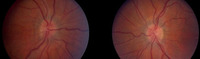

Idiopathic intracranial hypertension

MRI of empty sella on sagittal view

From the personal collection of Dr M. Wall; used with permission